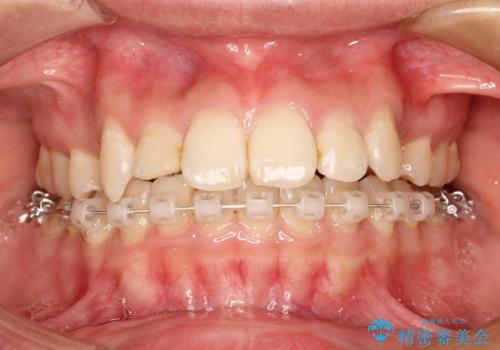

ハーフリンガル矯正 抜歯をして前歯を下げる

- ハーフリンガル

- 上顎の両側第1小臼歯抜歯による抜歯矯正を計画した。

上顎の抜歯により上の前歯の位置を大幅に後ろに下げることができます。